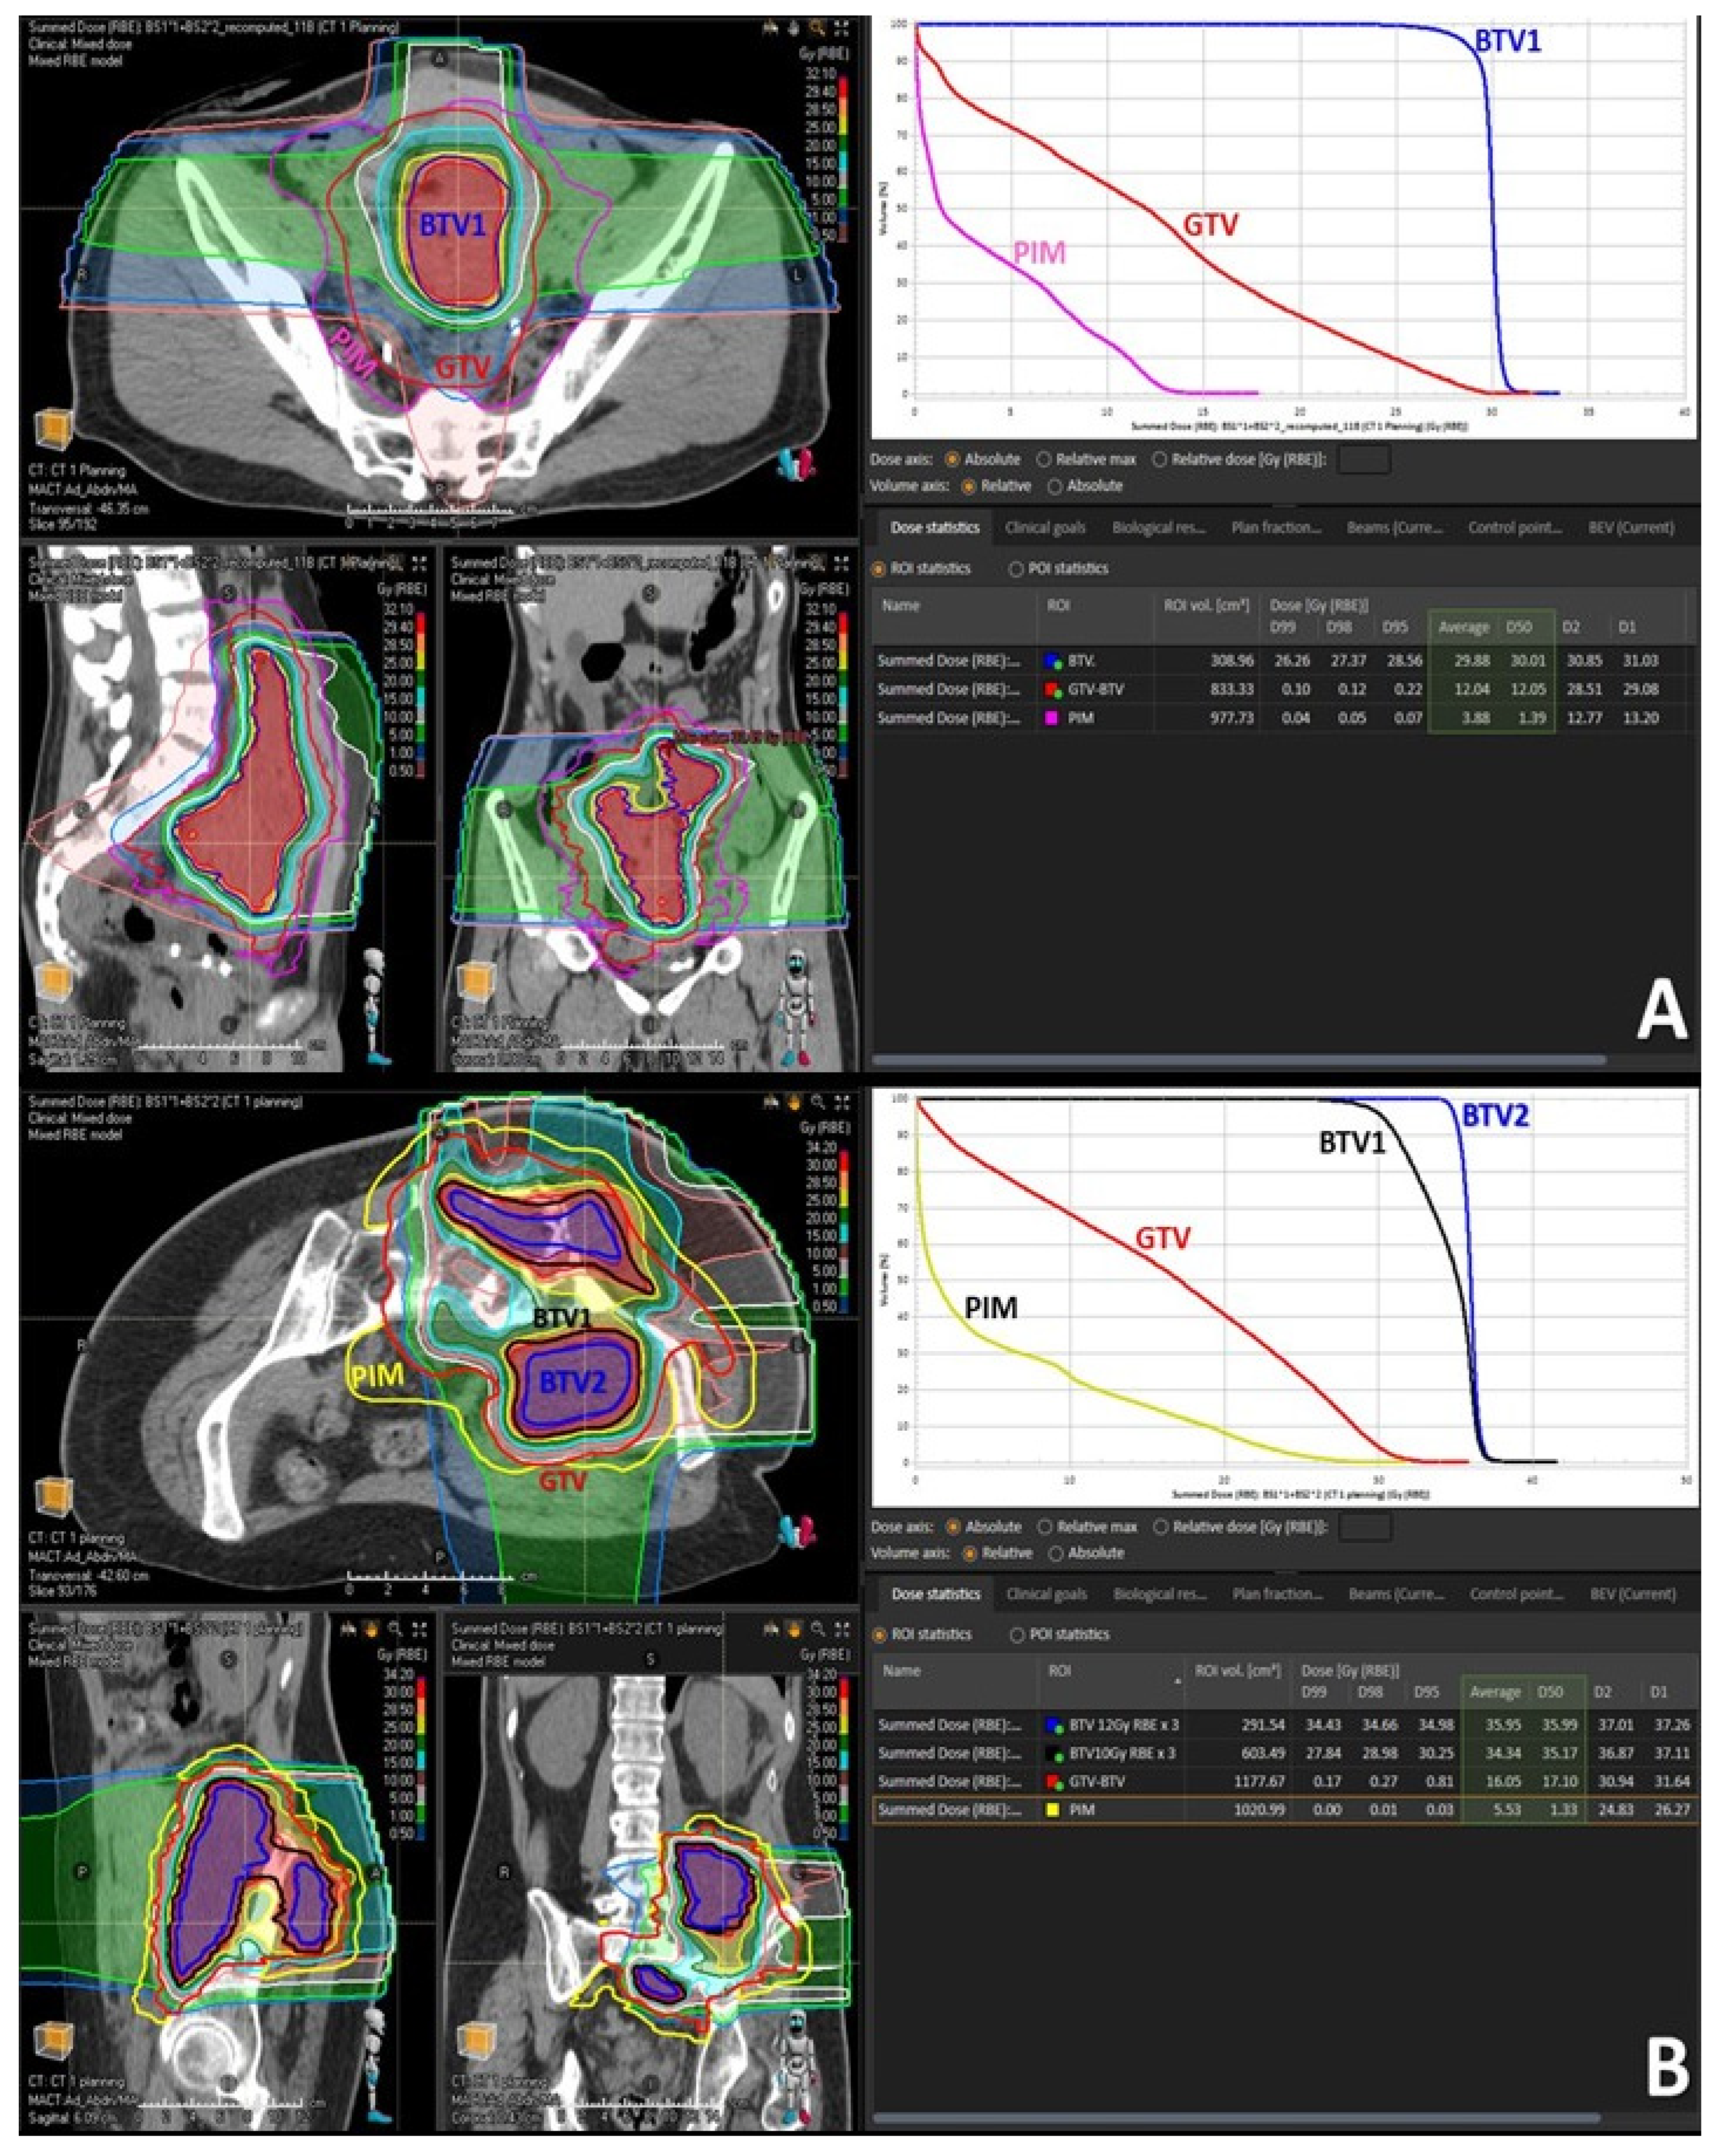

Figure 3. Treatment volumes for particle-based partial bulky tumor irradiation: the figure shows the targeted tumor sub-volumes with corresponding dose distribution delivered to the single subvolume-BTV1 (A) or two sub-volumes, BTV1 and BTV2, respectively (B). The highlighted green area in the dose statistics indicates the average and 50% dose of the targeted BTV volumes, non-targeted GTV volume and radiation-spared PIM volume. It is worth mentioning here that the mean radiation dose at the level of non-target GTV (GTV-BTV) was radio-biologically very low, hence non-tumoricidal, corresponding in the first case (A) to only BED2 Gy = 14 Gy while in the second case (B) to only BED2 Gy = 20 Gy.

To deliver sufficiently high and possibly heterogeneously distributed radiation dose at the level of the targeted BTV. The intended dose was in the order of 10–15 Gy per fraction. In order to address heterogeneity in radiation dose delivery, dose-gradients were created within the BTV, by creating an additional BTV (BTV2) within the former BTV (BTV1) by subtracting 5 mm from the BTV1 surface in all directions whenever tumor volume would permit it (Figure 2B and Figure 3B).

Achieving the BTV prescription goal was subordinated to the possibility of creating a sufficiently sharp dose fall off between the BTV surface and the GTV surface surrounded by the PIM and was proportional to the thickness of peripheral tumor tissue in between the BTV and GTV surfaces. Treatment plans were calculated to deliver 30–36 Gy in three consecutive fractions (10–12 Gy per fraction) to the BTV1, and 36–45 Gy (12–15 Gy per fraction) to the BTV2 so that at least 95% of the BTVs received as minimum 95% of the prescription dose. The choice of prescribing the fractional doses was driven by PIM-sparing: 12 Gy to the BTV1 with 15 Gy to the BTV2 were preferred if allowing planned PIM-sparing which was easier to achieve in particularly large tumors. Otherwise, the fractional dose was reduced to 10 Gy to the BTV1 with 12 Gy to the BTV2 to lower the dose received by PIM. In those patients in whom neither of the two goals was possible, only one BTV (BTV1) was created and treated either with 12 Gy × 3 or 10 Gy × 3 (Figure 2A and Figure 3A). Reported doses in Gy are RBE-weighted doses calculated from the physical dose using the LEM model for carbon ions [22] while for protons a fixed RBE of 1.1 was assumed.

Treatment characteristics are summarized in Table 3. Irradiated bulky-tumor sites were skull base (18%), head and neck (18%), lung (9%), abdomen (27%) and pelvis (27%). All three treated abdominal lesions were intraperitoneal. Mean tumor diameter and volume were 15.6 cm (range 6–27.5) and 1460 cc (range 76–5645.9), respectively. The mean volume of targeted BTV was 431.7 cc (range 36.1–1494) representing on average 29.6% of the mean GTV volume; i.e., approximately 1/3 of the GTV was targeted. Six patients (54%) were treated with 10 or 12 Gy delivered three times on consecutive days to the single BTV volume (BTV1). However, in the remaining five patients (46%) affected by particularly large tumors the dose corresponding to 10 and 12 Gy or 12 and 15 Gy was delivered three times to two tumor sub-volumes (BTV1 and BTV2), respectively (Figure 2 and Figure 3). Seven patients (64%) were treated with mixed proton and carbon ion therapy while four of them either with full proton (18%) or carbon ion (18%) therapy. The “immune-dose” in terms of the PIM-sparing was as low as it was initially intended: the total average mean dose was 5.8 Gy, D50 ≤ 2.8 Gy, D30 ≤ 0.7 Gy and D20 ≤ 0.2 Gy in three fractions.